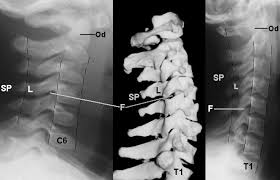

The transverse foramen is an opening on each of the transverse processes of the cervical spine which gives passage to the vertebral artery and vein and a sympathetic nerve plexus. There are two transverse processes that extend off each vertebra in the details: Transverse process fractures are common sequelae of trauma, although they are considered a minor and stable lumbar spine fracture. Transverse processes are typically fractured in direct blows from athletics touch or impact from falls from bikes/motorbikes or by heights. However, postmortem computed tomography (pmct) has made detection of this type of injury easy. There are two transverse processes that extend off each vertebra in the spine, one on each side. A transverse process fracture is a break in 1 or more transverse process. In 78% of transverse process fractures, ct scanning showed that the fracture extended into the transverse foramen. A transverse process fracture is considered as a rare injury. A transverse process fracture is a break in 1 or more transverse process. What is a transverse process fracture? Transverse process fractures caused by stress are likely under detected since even an acute transverse process fracture requires a high index of suspicion to be correctly identified(4,7). If ct confirms isolated injury lateral flexion/extension views are indicated to rule out dynamic instability.

However, postmortem computed tomography (pmct) has made detection of this type of injury easy. There are two transverse processes that extend off each vertebra in the details: What is a transverse process fracture? It may occur as an avulsion fracture due to strong contracture of the muscles. It occurs as a result of sudden and extreme trauma. If ct confirms isolated injury lateral flexion/extension views are indicated to rule out dynamic instability. Vertebral angiography, performed in eight patients with fractures involving the transverse foramen, showed dissection or occlusion of the vertebral artery in seven (88%) instances. This part extends out from the side of the main body of the bone (called the vertebral body). A transverse process fracture at the level of l5 is a surrogate marker of vertical instability of the pelvic fracture due to the attachment of the iliolumbar ligaments. We retrospectively reviewed the reports of lumbar spine and abdominopelvic ct scans from 2017 and 2018 to classify the types of spine fractures, their mechanism of injury, treatment and. Up to 60% of lumbar transverse process fractures identified on ct will be missed on plain radiographs. In 78% of transverse process fractures, ct scanning showed that the fracture extended into the transverse foramen. Transverse process fractures identified on helical computed tomography (ct) scans without the presence of any other fracture or.